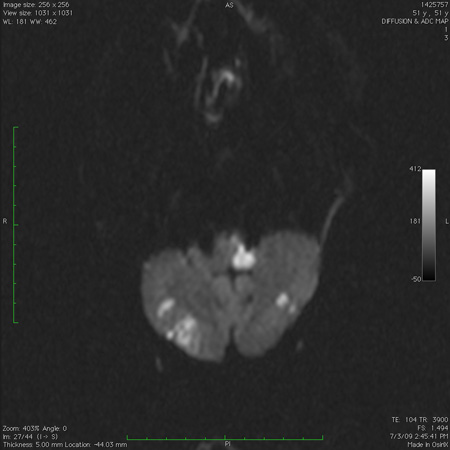

Work-up with imaging of the brain (CT scan, MRI with diffusion-weighted imaging sequence) is required to look for signal changes associated with stroke, demyelination, or cerebellitis.[128][132][133][134] CT imaging in children necessitates the use of dedicated paediatric protocols to minimise radiation exposure.[134][Figure caption and citation for the preceding image starts]: Acute bilateral cerebellar infarct, as seen on diffusion-weighted imaging sequence magnetic resonance imageFrom the collection of Dr S. H. Subramony; used with permission [Citation ends].